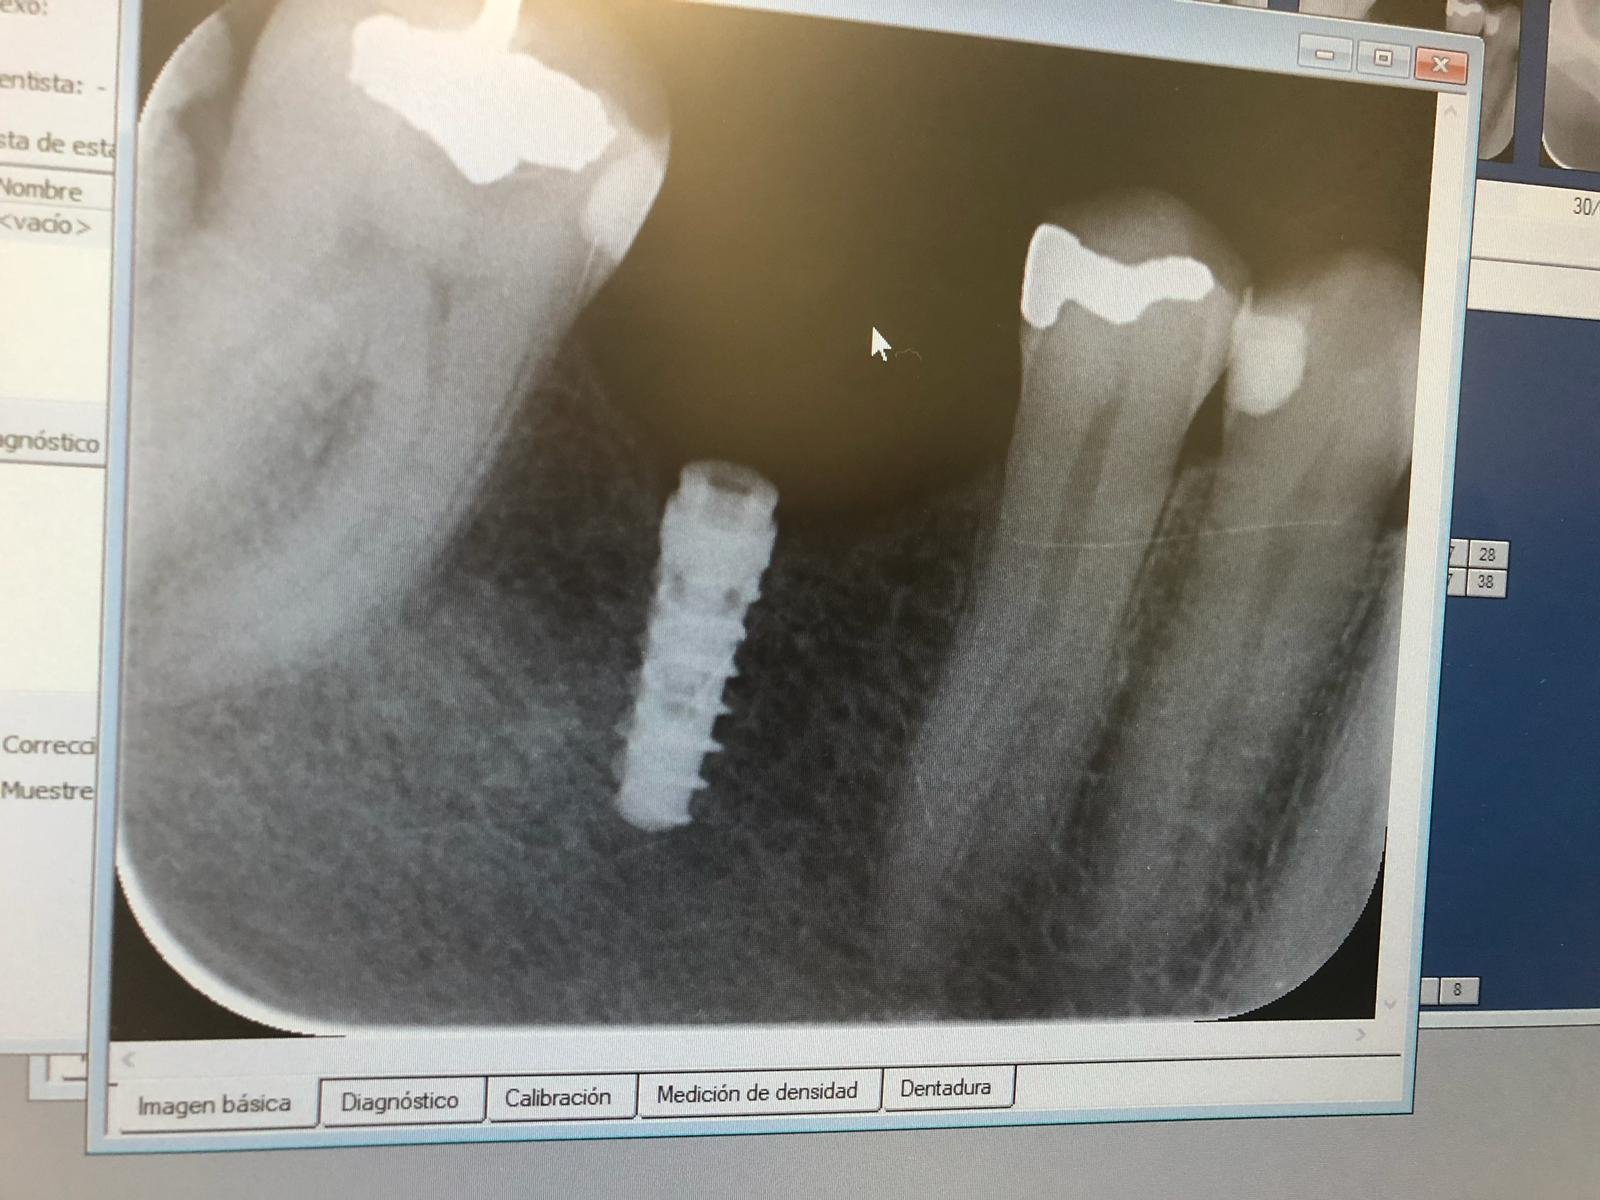

Ayuda para reconocer el Implante

Buenas noches, hace 2 meses le colocaron este implante con ese aditamento protesico para una protesis total removible, pero ese aditamento no ajusta bien y se desaloja del implante, pudieran [...]